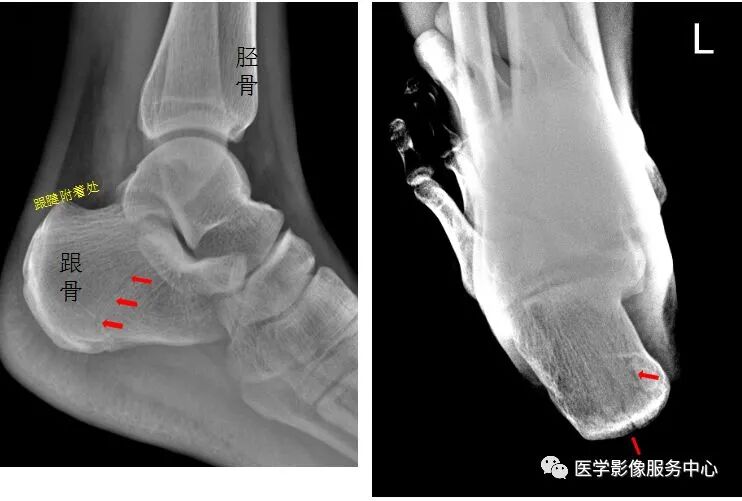

右足斜位示 右侧跟骨前部见骨折透亮线,右跟骨前部骨折。

Warmreminder:有一些微小的骨折很容易被忽视。

小妙招1.我会先观察患者精神状态;2.了解受伤部位软组织情况,有时为明确部位,也会亲自触诊。因为有些患者对自己受伤的部位不是很清楚,忘记自己怎么受伤。

左侧跟骨见骨折透亮线,后缘骨皮质连续中断,左侧跟骨骨折。